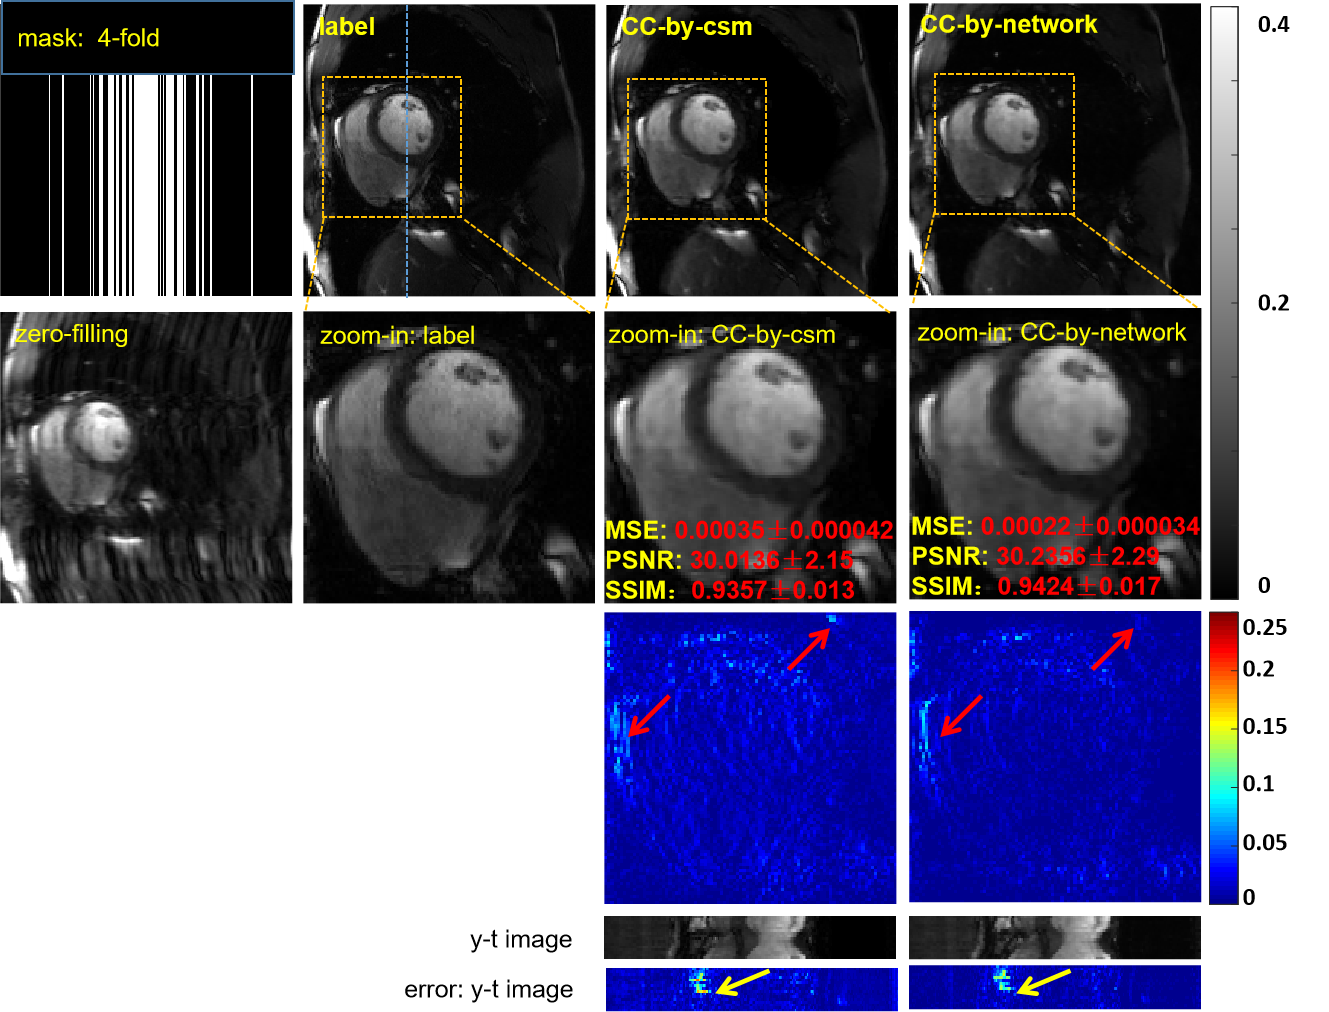

IV-C The Necessity of the Coil Combination Network

In the proposed method, a coil-combination network was used to explore the coil correlations and combine all the coil images. However, the way to optimally combine coil images via coil sensitivity maps (csm) is well understood. Therefore, the necessity of the coil combination network needs to be discussed. To demonstrate the effectiveness of coil combination by the coil combination network, we built a new model in which its coil combination was completed by csm estimated by ESPIRiT [44]. The hyperparameters used to estimate csm were selected as follows: calibration region: , kernel size: , , threshold: 0.95. We call this model CC-by-csm and the proposed model CC-by-network. The only difference between the two models is that the coil combination of one model goes through csm and the other through a network. The reconstruction results are shown in Fig.9. As shown by the error maps, the CC-by-network achieves a better reconstruction performance than does the CC-by-csm model, and its quantitative results are also improved to some extent. Therefore, our coil combination network is helpful in improving the reconstruction results.